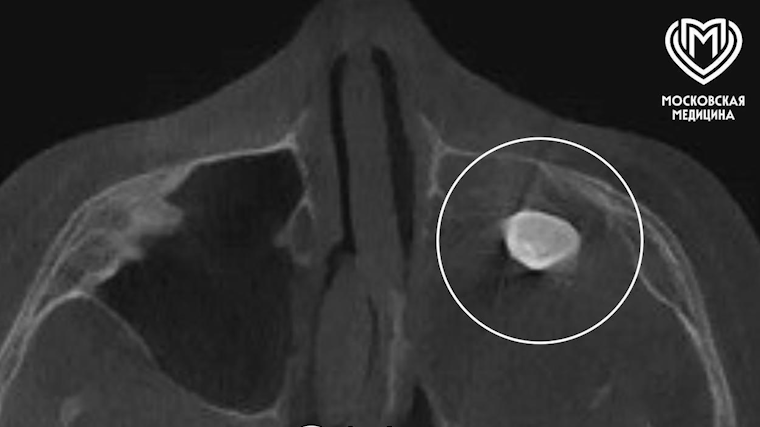

Столичные медики провели сложное хирургическое вмешательство 15-летнему юноше, у которого в полости носа обнаружили зуб. Об этом сообщили в пресс-службе департамента здравоохранения Москвы.

Специалисты приняли решение о проведении операции с доступом через верхнюю десну. В ходе вмешательства хирурги выявили новообразование, внутри которого находился зуб.

Удаленные ткани направили на гистологическое исследование. Выяснилось, что речь шла о доброкачественной тератоме — редком эмбриональном образовании, которое может содержать элементы, нехарактерные для области его расположения: волосы, костные структуры или зубы.